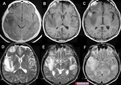

Bu testler, lenfoma ve diğer kan hastalıklarının varlığını değerlendirmek için kullanılır. 3. Görüntüleme TestleriHekim, lenfomanın yayılımını değerlendirmek için çeşitli görüntüleme testleri isteyebilir:

4. BiyopsiLenfoma tanısının kesinleştirilmesi için en kritik test biyopsidir. Biyopsi türleri şunlardır: